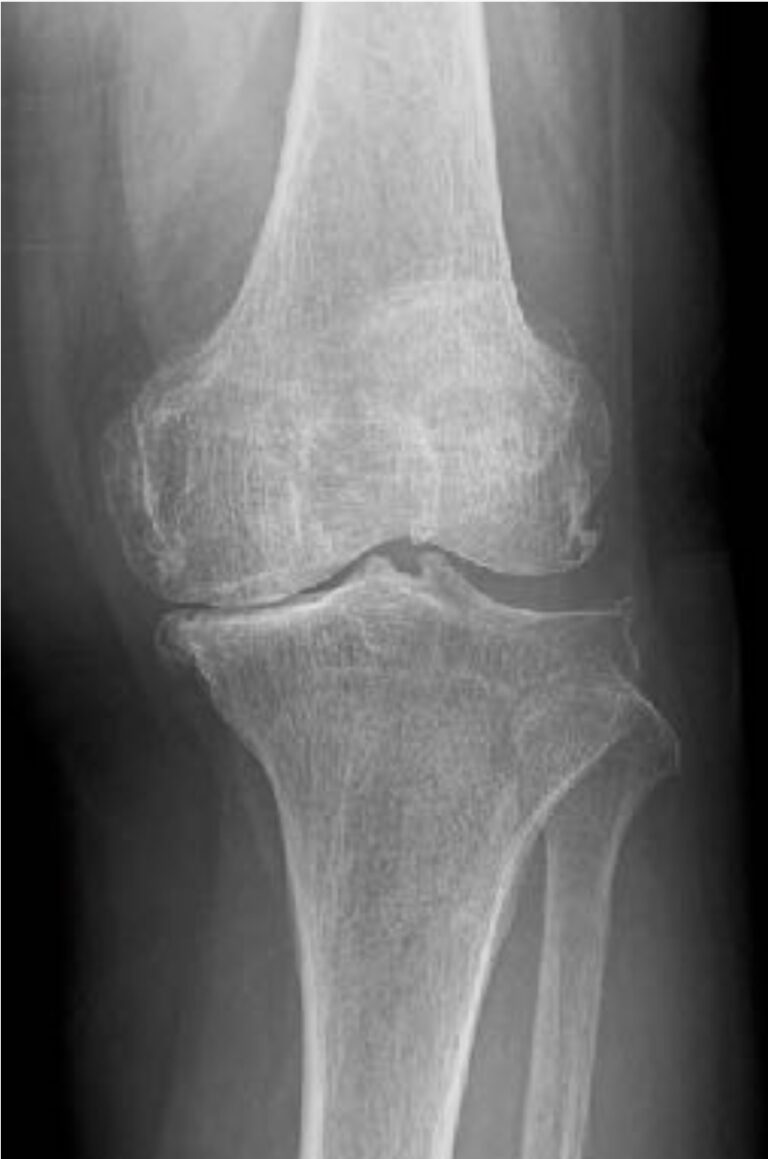

膝のレントゲン画像からわかる変形性膝関節症のKL分類について 足立慶友整形外科